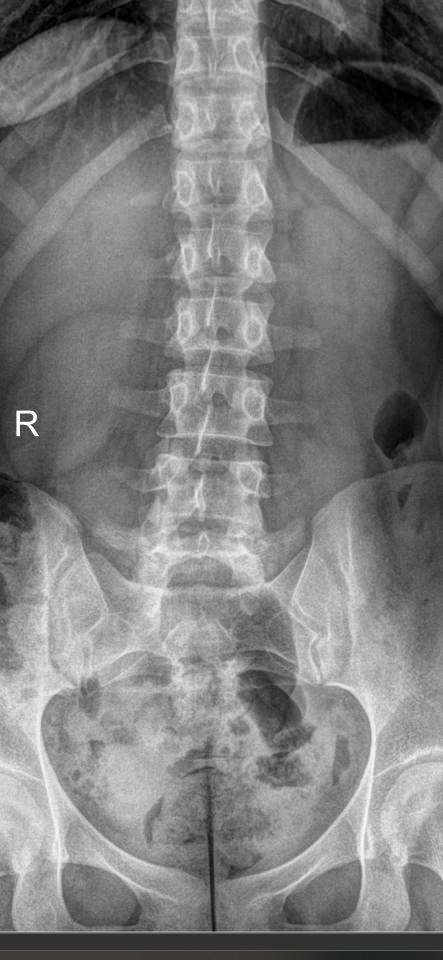

В исследование входит 3 снимка, показывающих состояние поясничного отдела в разных положениях. Однако бояться чрезмерного облучения не стоит: цифровые модели рентгеновского оборудования последнего поколения излучают минимально необходимую для четкого снимка дозу. После данного исследования количество облучения, полученного организмом, будет составлять едва ли десятую часть от допустимой годовой дозы.

На первом снимке будет видно, сохранен ли естественный поясничный лордоз или есть его изменения. На тестовых снимках будут видны:

• Изменение высоты межпозвонковых дисков при отсутствии патологий;

• Неизменность межпозвонковых пространств при наличии функционального блока;

• Смещение позвонков вперед или назад (вправо или влево) при их патологической подвижности;

• Деформация передней стенки позвоночного канала, когда подвижный позвонок смещен кпереди или кзади (вправо, влево).

Также будут видны остеофиты, опухоли, аномалии развития.

Процедура выполняется без подготовки. Пациент раздевается до белья, надевает защитный фартук и встает к пластине детектора. Чаще всего нужно определить смещение в передне-заднем направлении, поэтому пациент встает боком и поднимает руки за голову или держится ими за стул. Выполняется 3 снимка:

• В привычном  положении, то есть обычный боковой;

• В условиях максимального разгибания назад;

• В условиях сгибания вперед.

Реже требуются пробы для определения бокового смещения позвонков. Вы встаете к пластине спиной и, после снимка в прямой проекции, поочередно наклоняетесь вправо и влево. В запущенных случаях при сильной боли и невозможности выполнять пробы стоя, их делают сидя или лежа. Рентгенолаборант поможет вам правильно встать или лечь и безопасно наклониться. Каждый снимок длится около 1 секунды, во время съемки нельзя двигаться, но можно дышать.